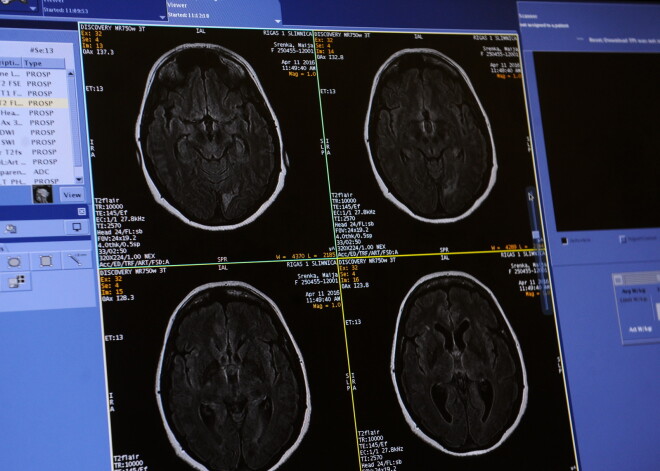

NET ir reta saslimšana, kas veidojas no neiroendokrīnajām šūnām, kuras mūsu organismā ir izvietotas visos audos – ādā, plaušās, gremošanas traktā, smadzenēs un citur. Dažkārt audzējs neizraisa nekādus simptomus vai tie ir viegli sajaucami ar citu slimību pazīmēm, diemžēl tādēļ bieži NET tiek atklāts tikai pēc 5 – 7 gadiem, kā arī sonogrāfijas vai plānveida operāciju laikā.